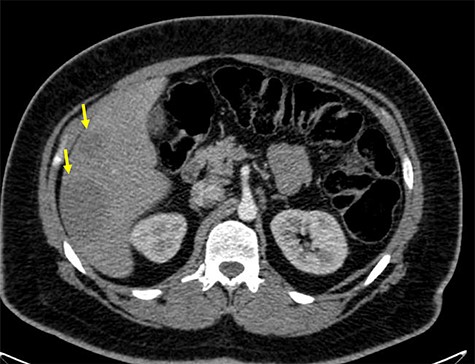

A 32-year-old man with no past medical or surgical history presented to the emergency department (ED) in April 2018, distressed and complaining of worsening pneumaturia for the past 3 days. The patient reported a 2-week history of polyuria, dysuria, suprapubic pain, tenesmus and inability to control his sphincters, prior to the ED-onset presentation. Further history revealed a 50-pound involuntary weight loss in a 5-month period, with partially treated urinary tract infections without resolution. He denied toxic habits, high-risk sexual behavior nor family history for colorectal cancer or inflammatory bowel disease. Based on the symptoms described, the rare triad of Gouverneur’s syndrome related to the EVF was considered. Physical evaluation revealed no palpable anorectal masses, adequate rectal tone and no visible gross blood. Urine analysis showed pyuria, hematuria, proteinuria with urine culture positive for Escherichia coli. Abdominopelvic computed tomography (CT) scan showed circumferential wall thickening of the rectum with surrounding fat stranding and numerous prominent pelvic lymph nodes (Fig. 1). Additionally, the scan showed pericolonic gas and fluid collection with a fistulous tract adjacent to the proximal rectum and the bladder (Fig. 2). In Figure 3, two hepatic hypodense lesions located in the right lobe of the liver were identified suggestive of metastasis. During colonoscopy, at approximately 20 cm from the anal verge a large, firm, irregular, friable, concentric mass was identified obstructing 95% of the lumen (Fig. 4). During surgery, the mass was not amenable for resection, due to its low pelvic location and size; a loop colostomy was performed for decompression, with liver tru-cut needle biopsy. Intraoperative cystoscopy was unsuccessful in placement of ureteral stents due to tumor invasion to the bladder.

Axial abdomen and pelvis CT scan showing hepatic hypodense lesion and possible liver metastasis (yellow arrow).